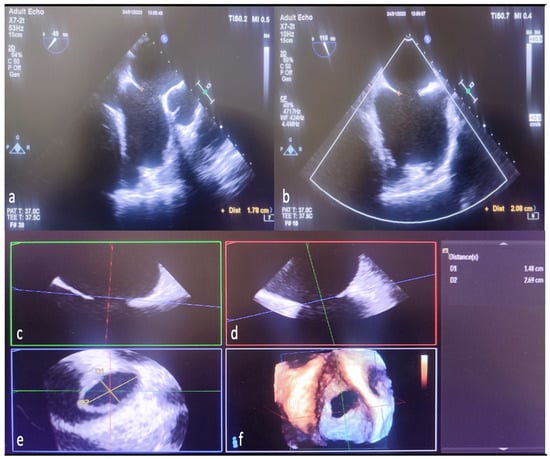

The analysis of 3D image data was performed offline in accordance with the guidelines [11]. Since the shape and size of the defect change dynamically throughout the cardiac cycle, both minimum and maximum ASD aperture diameters were measured at the end of the systole in the 2D ASD imaging. In addition, residual rims in 3D were obtained in the face view at the end of the systole during the largest defect opening. In addition, cropping (auto crop and iCrop) was performed to determine the measurement, axis, and localization of some rims. Defect diameters were measured offline with the multiplanar reconstruction (MPR) method from 3D zoom datasets in QLAB (QLAB version 10.5 software (Philips Medical System, Best, The Netherlands). The mid-esophageal short- and long-axis examination of ASD by 2D TEE is shown in Figure 3a,b. Reconstruction of different planes in 3D TEE multiplanar examination shown in Figure 3c,d. The measurement of ASD diameters by MPR method in the 3D TEE examination is shown in Figure 3e,f.

Figure 3.

Measurement of defect diameters with MPR in 3D TEE and comparison with 2D TEE. The length ASD of the was measured as 1.78 cm on 2D TEE mid-esophageal short-axis imaging (a). The same defect was measured as 2.08 cm in bicaval examination with 2D TEE (b). Display ASD diameters in multiple planes to generate MPR from 3D TEE zoom mode examination datasets (c,d). Length measured from the anteroposterior (short-axis-minimum diameter) aperture plane (red line) in multi-planer examination (1.78 cm defect measured in 2D TEE) (c,e,f). Again, the specified length (measured by 2D TEE) from the superoinferior (bicaval-long-axis-maximum diameter) aperture plane (green line) is seen as 2.08 cm (d–f). Naturally, in the final image created with MPR as a result of combining the planes (indicated by red, green, and blue lines), it is seen that the defect is ellipsoid, and the real minimum diameter (D1 yellow line-short axis) is 1.48 cm, the real maximum diameter (D2 yellow line-long axis) is 2.69, measured in cm (e). MPR, multiplanar reconstruction; 2D, two-dimensional; 3D, three-dimensional.